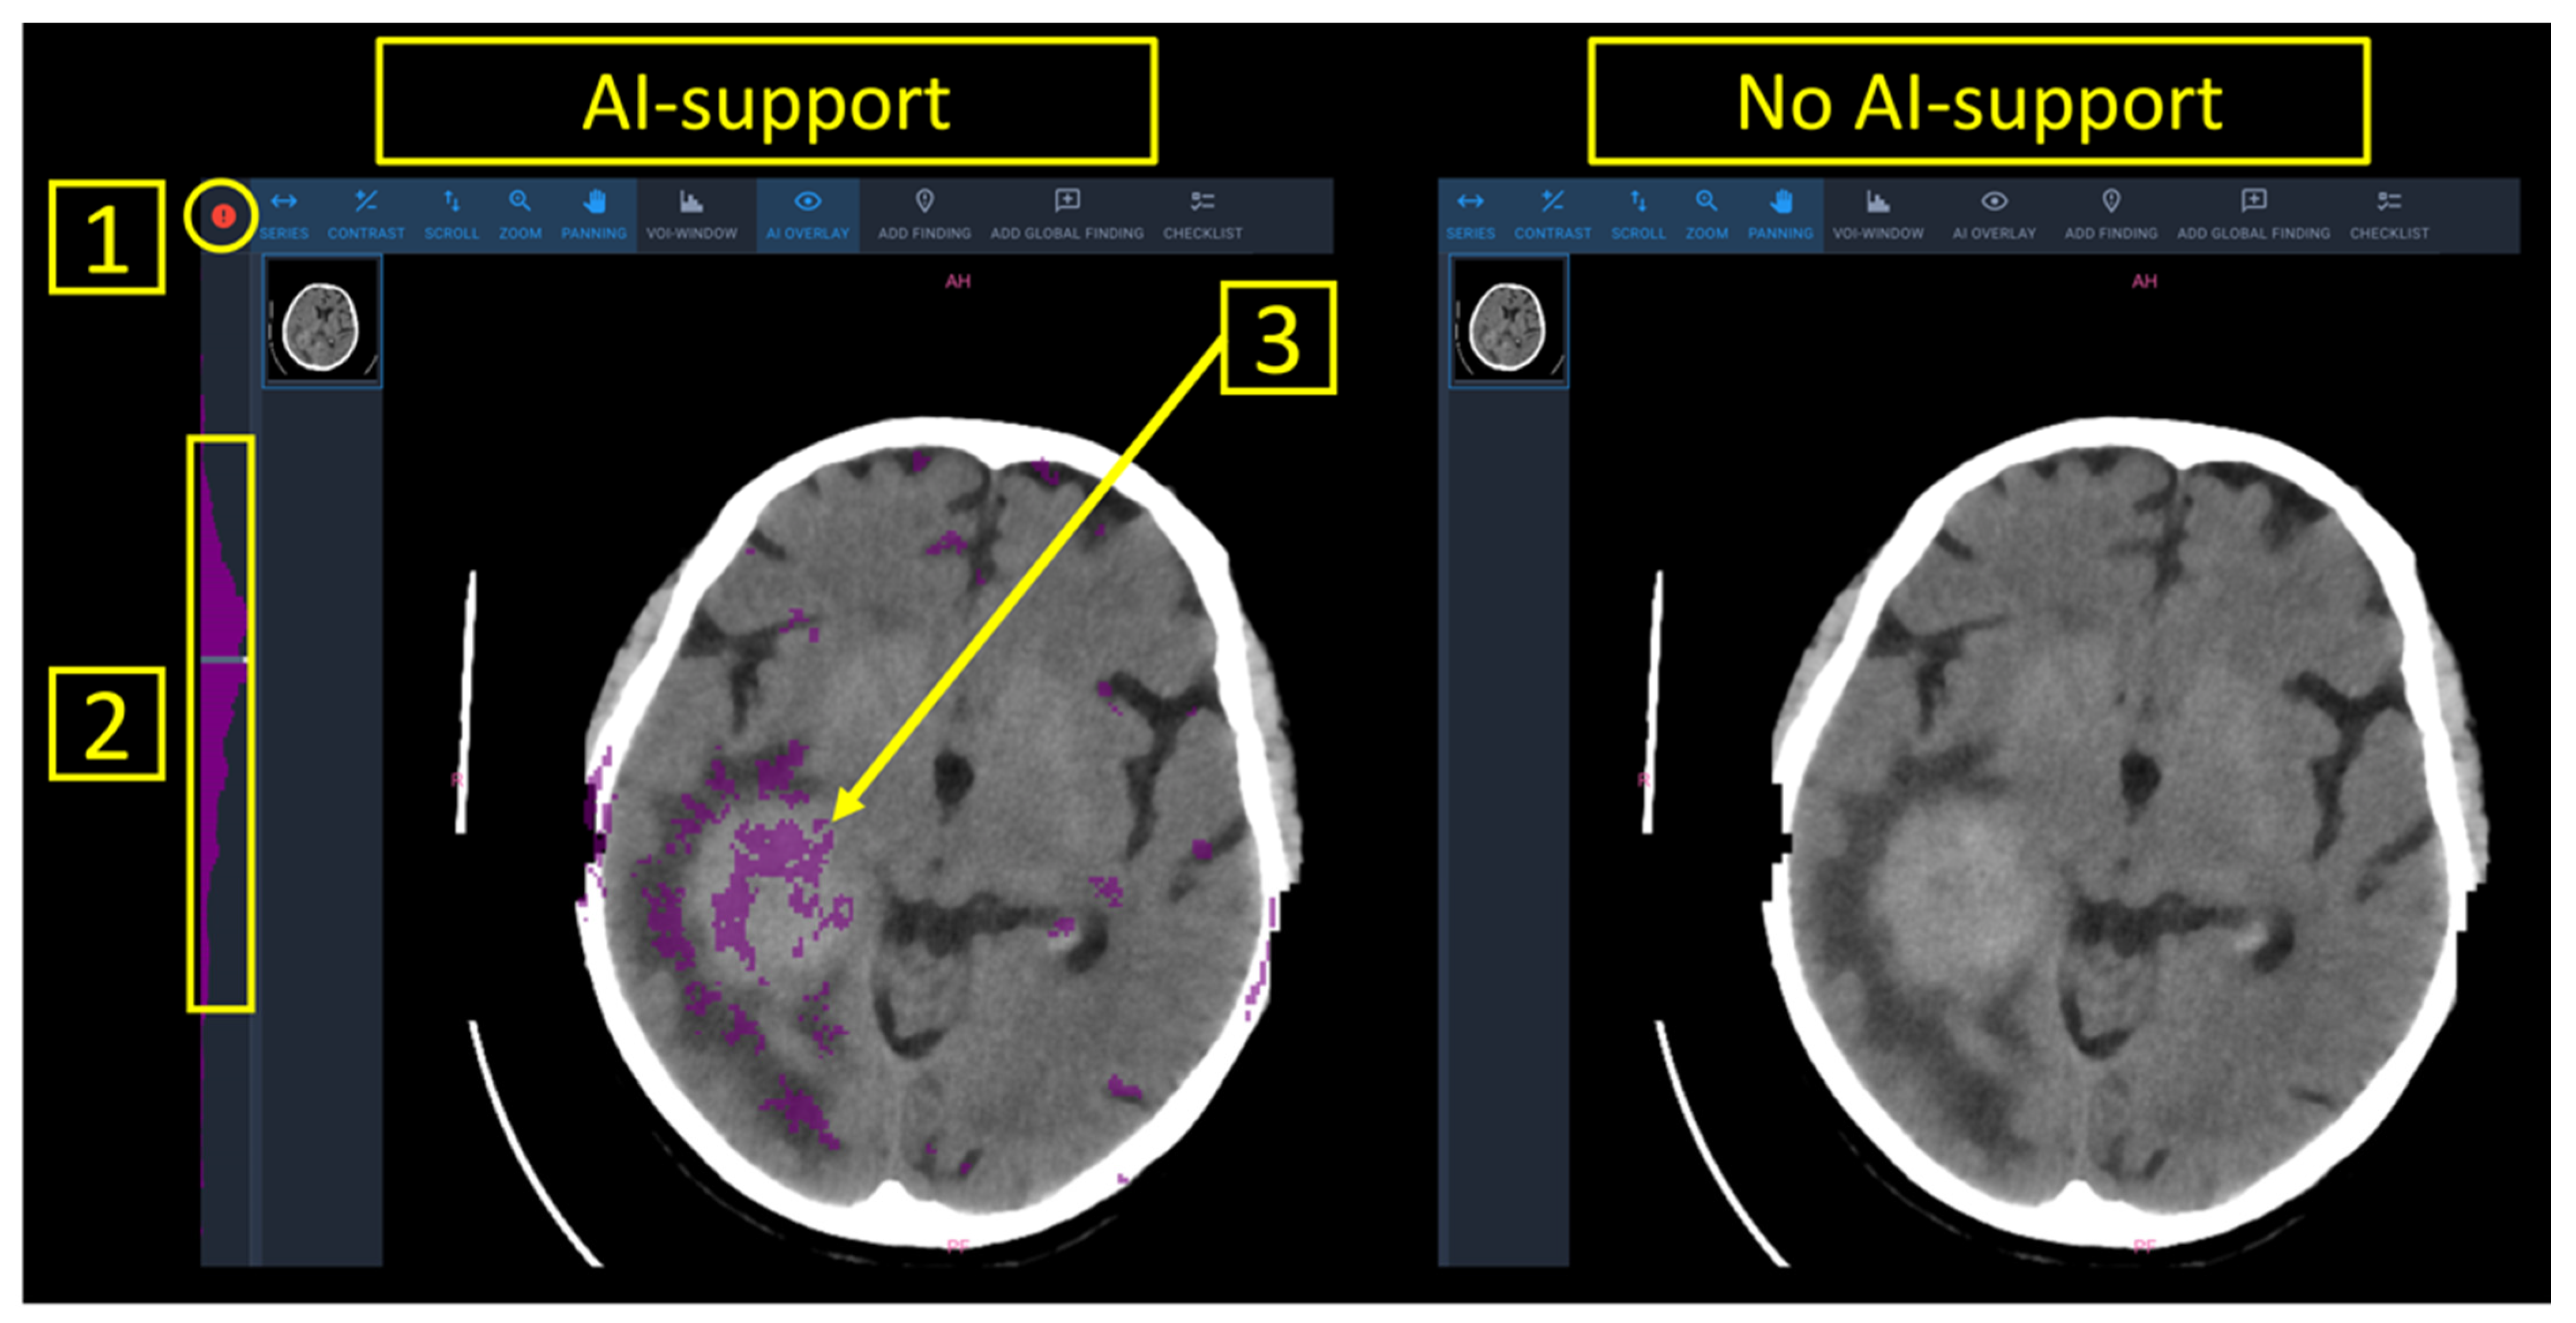

2.2. Anomaly Detection Tool